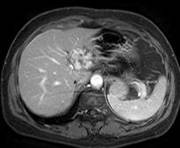

图示 : 小肝癌 的三期扫描,增强早期病灶明显强化,门静脉和延迟期呈低密度。